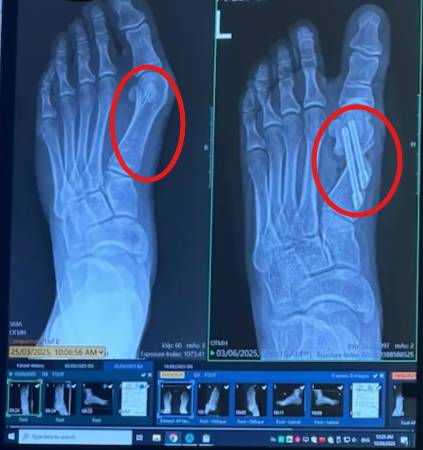

¿Por qué fracasan las cirugías para el juanete?

Hasta un 30–50% de las cirugías para el juanete fracasan o terminan provocando rigidez prolongada, cicatrices o la reaparición del dolor.

¿Recuperación? Calcula de 6 a 12 semanas sin poder apoyar el pie, con muletas y el riesgo de recaída si no usas plantillas ortopédicas de por vida.

Estas cirugías no abordan el verdadero problema — simplemente cortan y usan tornillos para volver a unir las articulaciones de los dedos.